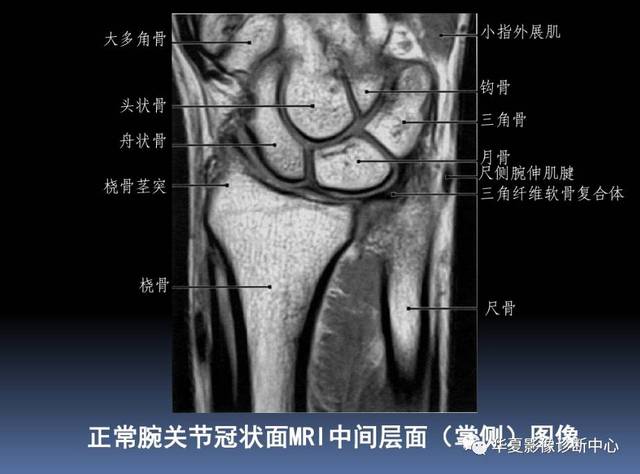

【影像基础】腕关节mri解剖及常见病诊断